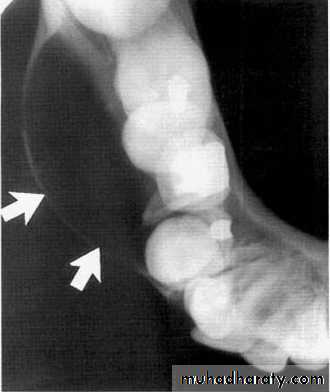

The radiograph shows erosion of the alveolar bone (o) and elevation

of the floor of the nasal fossa (arrows).• Globulomaxillary Cyst

• Located between the lateral incisor & cuspid teeth, the teeth are vital . Radiographically;an inverted• pear shape radiolucency

• between the roots of lateral & cuspid teeth, the roots of teeth pushed apart.

• Treatment by excision.